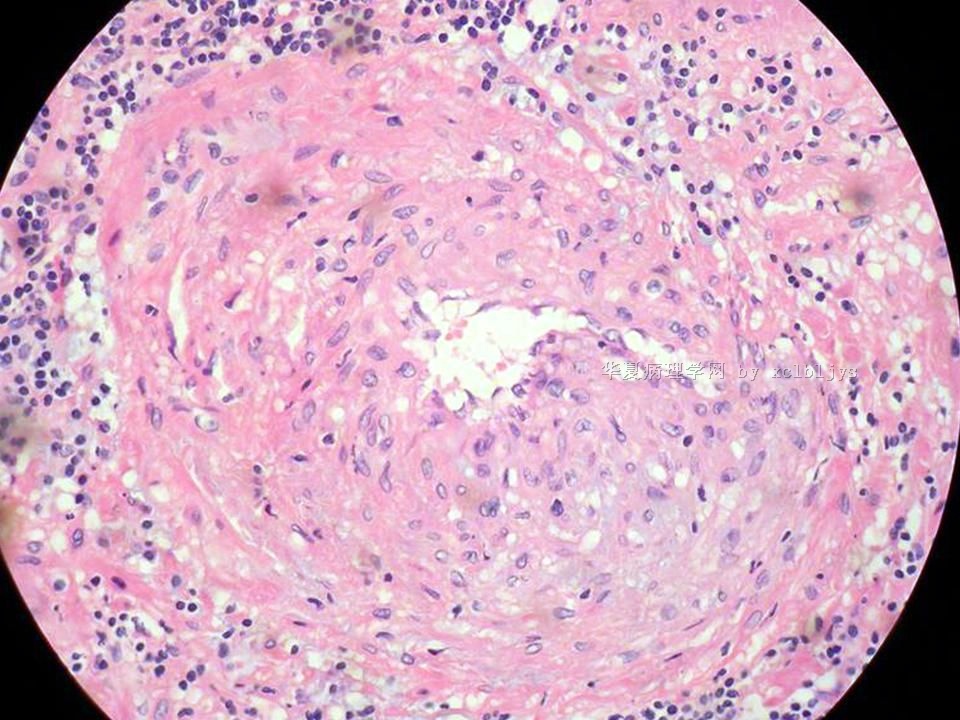

| 以下是引用xclbljys在2010-12-22 17:20:00的发言: 本例我们科室医生有两种意见:一种是炎性假瘤;第二种意见是炎性假瘤伴局限性Wegener肉芽肿。 依据是眼眶内肿块含有大量的动脉内膜炎改变,浸润的炎细胞有淋巴细胞、浆细胞、嗜中性粒细胞和嗜酸细胞等,如图16所示,炎细胞已经浸润动脉壁全层,应符合坏死性小动脉炎,但尚不能确定动脉壁弹力纤维层的破坏。 请各位老师点评! Wegener肉芽肿多发生在上呼吸道、肺、肾脏和皮肤等器官与组织。坏死性血管炎需证实有纤维素样坏死。小动脉炎多在皮肤病变比较明显。本例的小动脉炎或许是炎症引起的继发性改变。需要完善病史,查血免疫指标,看有没有系统性疾病。如果没有系统性疾病,还是考虑慢性炎症继发小血管炎。

血管炎是正常营养/供给血管的炎症性病变,而不是增生血管的炎症。血管炎往往有明显的临床相应症状,如皮疹。典型的Wegerner肉芽肿病有三联症(上呼吸道、肺、肾脏病变)。血管炎不仅是有炎症细胞,同时有血管壁的变性、坏死(纤维素样), 内皮细胞的变质和增生,炎症细胞浸润(包括中性粒细胞、淋巴细胞、组织细胞、嗜酸性细胞、巨细胞等)。不同类型的血管炎累及的血管大小、炎症细胞的类型、有无肉芽肿改变都不相同。血管炎的病因可以是过敏、自身免疫、胶原性疾病、感染等多种因素。